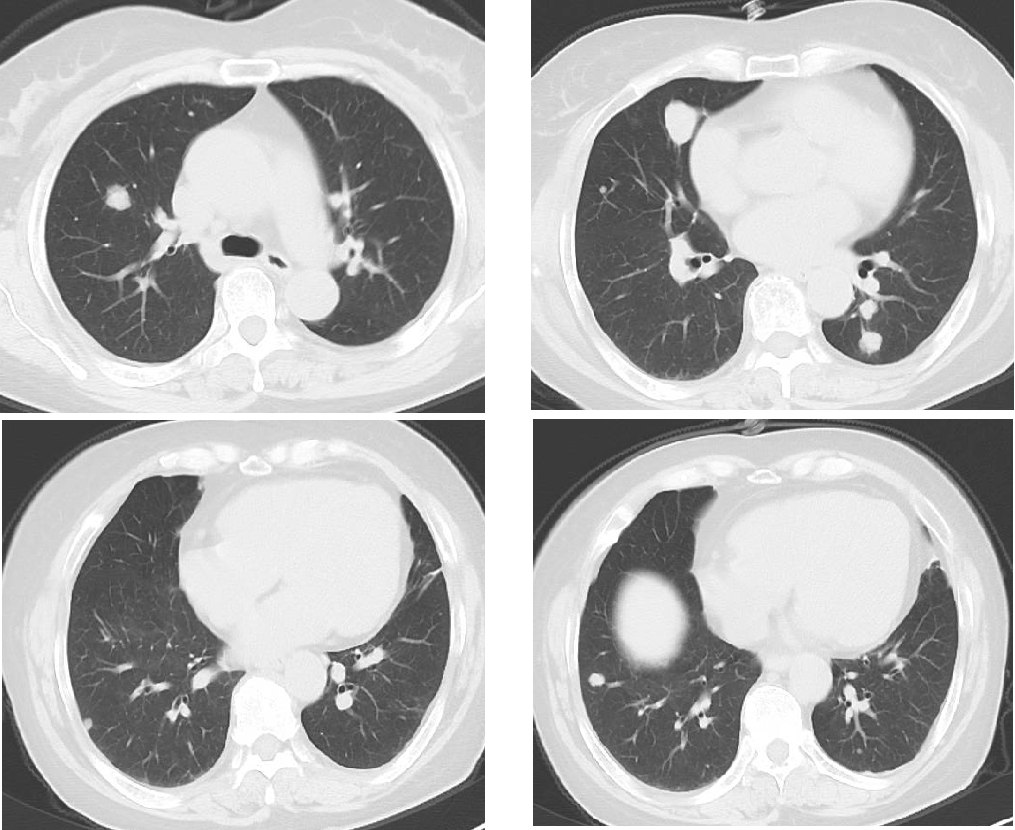

一 专家访谈 专家简介 于国华 教授 潍坊市人民医院 潍坊市肿瘤防治中心主任、潍坊市人民肿瘤医院院长、GCP机构副主任 潍坊市科技智库首席专家,省级重点学科负责人 中国临床肿瘤学会(CSCO)理事 山东省抗癌协会常务理事 潍坊市抗癌协会理事长 中国老年学学会舒缓治疗分会常务委员 中国老年学学会老年肿瘤专业委员会 中国老年学学会老年肿瘤专业委员会(CGOS)分子靶向分委会、肺癌分委会常务委员 山东省医学会肿瘤微创治疗分会副主任委员 山东省医学会姑息医学分会副主任委员 山东省肿瘤微创质量控制中心副主任委员 山东省医师协会肿瘤化疗医师分会副主任委员 山东省抗癌协会肿瘤化疗分会、肺癌分会、靶向治疗分会、心理治疗分会副主任委员 潍坊市医学会肿瘤化疗分会主任委员 潍坊市中西医结合学会肿瘤专业委员会主任委员 潍坊市肿瘤化疗专业质量控制中心主任 Q1 随着检查手段不断丰富,晚期结直肠癌的全程管理成为必然趋势。请您谈一谈我国在结直肠癌全程管理方面取得了哪些成果,未来应该朝着哪些方向努力? 我国在结直肠癌全程管理方面的进步成果,大概可以分为三个方面。 第一方面,随着医疗检测技术和诊疗理念的革新,我国早筛早治取得了良好进展。60~80年代我国检查技术相对落后,主要为粪便潜血试验展开有关肠道检查,而随着内镜技术的发展,肠镜检查逐渐普及,提高了结直肠癌早期患者的诊断率,推进了我国早诊早治的策略,使更多患者及早发现疾病并接受治疗。 第二方面,我国医疗制度具有优越性。随着我国全民医保的全面落实,“全民健康”理念的普及,就诊路径日益优化,更加快速便捷,使患者尽早获得诊断和治疗。 第三方面,国家癌症中心以及有关学协会的成立,推动了我国整体诊疗水平的不断提高。不仅为基层和各级医院搭建了良好的学习平台,推动了临床医生的再学习、再教育,也使得规范化诊疗、多学科协作(MDT)等优秀诊疗理念得以推广和实践。 第四方面,在内外科领域,药物治疗和手术治疗也是发展比较迅速。我国加速推进新药研发和医药服务创新,使更多药物尽快落地,惠及我国患者。相有关学协会积极组织形成了具有实践和指导意义的全程管理专家共识/指南,包括患者自身情况的评估、围手术期管理、治疗药物的选择、各线药物治疗方案、药物不良反应管理等。 关于结直肠癌全程管理未来的发展,需要以预防、规范化治疗和新药研发为抓手。 第一方面,预防是结直肠癌管理的第一步,未来有待在国家层面开展大规模的宣传教育,科普健康生活方式,令群众了解结直肠癌危险因素,从源头降低结直肠癌的患病风险。 第二方面,早筛早诊尽管已经取得显著成效,等仍需要深入基层,覆盖偏远贫困地区,使更多结直肠癌患者能够在早期发现,尽早干预,提升结直肠癌患者整体生存和预后。 第三方面,结直肠癌诊疗规范有待进一步提升,尤其需要在基层医疗单位加强规范化诊疗的理念。 第四方面,精准医学时代背景下,我们希望未来随着分子水平研究和精准医学研究的进展,在疗效监测和复发监测方面能使用更精准、更有价值的分子标志物动态监测。在手术前判断患者是否需要先做辅助化疗,在手术后判断是否需要进行复发监测,通过分子标志物可以更早地提示未来是否会复发,是否需要提前干预,如果复发,分子标志物可以再次作为监测指标指导治疗。 第五方面,我们还需加大研发力度,开发更多新机制、新靶点的药物,进一步提升晚期结直肠癌的疗效。 Q2 长期以来,化疗始终是肿瘤治疗领域的基石。其中,曲氟尿苷替匹嘧啶片(TAS-102)作为新型口服化疗药,问世以来不断为结直肠癌领域打开新的治疗格局,请您谈谈该药在中国的上市是基于怎样的研究成果? TAS-102在中国的获批是基于国际多中心 RECOURSE 研究和亚太TERRA研究的结果。RECOURSE研究是TAS-102的国际多中心Ⅲ期临床研究,显示TAS-102较安慰剂显著延长中位OS时间(7.1个月对比5.3个月)和中位PFS时间(2.0个月对比1.7个月),死亡风险和疾病进展风险分别降低32%和52%。此后,有众多中国临床专家参与的TERRA研究,证实了TAS-102在亚洲人群的安全性和有效性,TERRA研究重复出了RECOURCE研究的结果,TAS-102组患者的中位OS时间(7.8个月对比7.1个月)和PFS时间(2.0个月对比1.8个月)得到显著改善,死亡风险和疾病进展风险分别降低21%和57%。这两项关键研究成功改写了包括ESMO、NCCN、CSCO等中外权威指南的推荐。 而且,这两项研究中,TAS-102的不良反应均以血液学毒性为主,有症状的不良反应发生率低。鉴于其良好的安全性和耐受性,TAS-102与其他药物联合用于肠癌也在研究中进行了探索并取得了不错的结果。 Q3 晚期结直肠癌的发生通常预示着预后相对较差、患者生存期不长,但依然有治愈的可能,这关系到临床治疗用药方案的决策。今年上半年发布的CACA-RC指南推荐不适合强烈治疗患者应用TAS-102联合贝伐珠单抗,作为晚期不可切除结直肠癌姑息一线治疗方案。请您谈谈该推荐治疗对我国晚期不可切除结直肠癌的临床治疗产生了怎样的影响? 晚期转移性结直肠癌的标准化疗方案在指南中是以奥沙利铂或伊立替康为基础的FOLFOX和FOLFIRI方案,在此基础上,可以联合西妥昔单抗或贝伐珠单抗,但是,依旧有部分患者身体状况无法耐受加强化疗,少数患者因为高敏可能出现药物过敏,针对这一类患者,治疗方案的选择非常有限且预后情况并不理想。临床上往往推荐口服化疗药物+贝伐珠单抗方案。 2022年CACA-RC指南基于TASCO1研究的结果,推荐拒绝静脉化疗或不能耐受强烈治疗、易敏的晚期肠癌患者姑息一线选择TAS-102+贝伐珠单抗方案。TASCO1研究是一项旨在随机比较TAS-102+贝伐珠单抗和卡培他滨+贝伐珠单抗在一线治疗不可接受强烈治疗的不可切除转移性结直肠癌的Ⅱ期研究。研究结果显示:TAS-102组延长患者mPFS时间1.41个月(9.23个月对比7.82个月);延长患者mOS时间4.64个月(22.31个月对比17.67个月)。安全性分析也提示TAS-102+贝伐珠单抗治疗具有良好的耐受性,它最常发生的3/4级不良事件是中性粒细胞减少症。严重的发热性中性粒细胞减少症发生率约为4%。TAS-102+贝伐珠单抗方案因其高效、低毒的特点为不适合强烈治疗的转移性结直肠癌患者及老年患者带来了新的希望,其疗效与生存获益令人期待。 Q4 近年来,结直肠癌领域联合治疗的研究探索不断取得进步。请您谈谈,还有哪些研究进展为TAS-102联合贝伐珠单抗奠定一线治疗地位打下基础? 近年来,多项临床研究不断为TAS-102的临床可及性打下良好基础,DANISH研究将TAS-102与贝伐珠单抗联合用于转移性结直肠癌二线及以上治疗,发现联合组较TAS-102单药组疗效更好,中位PFS时间(4.6个月对比2.6个月)和OS时间(9.4个月对比6.7个月)显著延长,且联合组安全性可控,未出现非预期的不良反应。日本C-TASK-FORCE研究和欧洲DANISH研究均显示,对于PS为0~1分的转移性结直肠癌患者,TAS-102+贝伐珠单抗三线治疗实现了超过4.5个月的中位无进展生存期(PFS),超越了既往单药三线治疗的总体水平,且未显著增加不良事件(AEs)。TAS-102+贝伐珠单抗4周方案治疗转移性结直肠癌显示了良好的抗肿瘤活性。日本BiTS研究确证了双周方案可在不影响疗效的前提下,明显降低中性粒细胞减少症发生率。日本KSCC 1602研究和欧洲TASCO1研究都成功探索了FTD/TPI+贝伐珠单抗用于转移性结直肠癌一线治疗的疗效和安全性。 二 病例分享 专家简介 任海朋 主任 潍坊市人民医院 潍坊市人民医院肿瘤内科副主任,副主任医师 中国抗癌协会肿瘤微创治疗专业委员会委员 中国抗癌协会肿瘤消融治疗专业委员会委员 山东省健康管理协会消化道肿瘤防治分会副主任委员 山东省抗癌协会青年理事会常务理事 山东省医学会肝脏肿瘤多学科联合委员会委员 山东省抗癌协会消化道肿瘤分会委员 潍坊市医学会结直肠癌多学科联合专委会副主任委员 潍坊市医学会肿瘤微创治疗专业委员会副主任委员 潍坊市医师协会肿瘤化疗医师分会副主任委员 肖海凤 医师 潍坊市人民医院 潍坊市人民医院肿瘤内科主治医师,硕士 山东省抗癌协会化疗分会青年委员会委员 山东省疼痛医学会癌痛与姑息治疗专业委员会委员 山东省医学会科学普及分会肿瘤科普学组委员 山东省医学会精准医学分会消化道肿瘤学组委员 潍坊市医学会化疗专业委员会委员兼秘书 潍坊市抗癌协会乳腺癌专业委员会委员 潍坊市抗癌协会妇科肿瘤分会委员 潍坊市医学会第三届肛肠外科专业委员会青年学组委员 01 基本情况 基本情况:史xx,女,57岁,既往体健,无特殊病史,无家族史。 简要病史: 2020.1 患者出现大便带血,为暗红色,与大便相混,伴大便次数增多3~4次/天,大便不成形,伴肛门坠胀及里急后重感。 2020.4 就诊于潍坊市人民医院消化内科门诊,行肠镜示距肛门10cm环周隆起性病变,肠腔狭窄,镜身不能通过,考虑直肠癌,活检病理示腺癌(中分化)。 2020.4.16 就诊于我院肛肠外科一区,行胸腹盆部CT提示乙状结肠占位,考虑肿瘤,盆腔肿大淋巴结,双肺多发转移瘤。 诊断:直肠癌(cT3N+M1a,IVa期)。 2020.4.18 肺多发转移(CT) 2020.4.18 直肠原发灶(CT) 2020.5.12 基因检测 KRAS:Exon2、Exon3无突变;NRAS:Exon2、Exon3 无突变;BRAF:Exon15(V600E)无突变。UGT1A1*28:TA6/7,UGT1A1*6:G/G。MSS。 02 治疗经过 因直肠原发灶进镜困难,肠腔狭窄,发生肠梗阻风险较大,建议先行原发灶切除,后行全身抗肿瘤治疗。 2020.4.23 行直肠癌根治术(前切除术)+回肠预防性造口术+肠粘连松解术。 术后病理 一线治疗经过 2020.5.18至2021.1.31 行奥沙利铂甘露醇注射液225mg d1+卡培他滨1.5g bid d1-14方案化疗8周期。 不良反应:胃肠道反应不著,骨髓抑制最重2度。 疗效评价:5周期后疗效评价为PR,8周期后疗效评价为PD。 双肺转移灶(一线) 二线治疗经过 入住我科,ECOG 0分,身高159cm,体重65kg,体表面积1.64m2。 2021.3.9、2021.3.29、2021.4.12、2021.5.6、2021.5.25、2021.6.21、2021.7.9、2021.7.28、2021.8.15行西妥昔单抗800mg d1+伊立替康300mg d2+氟尿嘧啶650mg iv,4000mg civ 46h+左亚叶酸钙325mg d2化疗9周期。 不良反应:胃肠道反应不著,骨髓抑制2度。 疗效评价:缩小的SD。 双肺转移灶(二线) 三线治疗经过 2021.9至2022.5.6 口服呋喹替尼5mg qd d1-21 q28d治疗。 不良反应:高血压病1级,轻度肝功损伤。 疗效评价:2个月后疗效评价PR,7个月后肺内病灶增大,肝内出现新发病灶,疗效评价PD。 双肺转移灶(三线) 肝脏(新发病灶) 四线治疗经过 2022.5至今 开始应用贝伐珠单抗300mg d1联合TAS-102 55mg bid d1-5双周治疗。 不良反应:高血压2级,继发性甲状腺功能减退,白细胞减少I度,中性粒细胞减少2度,贫血1级。 疗效评价:PR。 03 病例小结 04 心得体会 TAS-102是一种新型口服细胞毒药物,是口服的氟尿嘧啶类药物,作用机制不同于氟尿嘧啶,可用于氟尿嘧啶耐药患者。 国际RECORSE和亚太TERRA研究证实,TAS-102在mCRC治疗中具有一致的疗效和安全性:1.显著延长mCRC患者生存期,降低死亡和疾病进展风险,尤其对于≥65岁患者获益更显著;2.显著延缓体能下降,为持续治疗提供体能储备;3.主要不良事件为血液学毒性。 双周TAS-102联合贝伐单抗不仅不降低疗效,而且明显降低中性粒细胞减少症发生率。 *本文仅代表专家观点,并经专家审校。